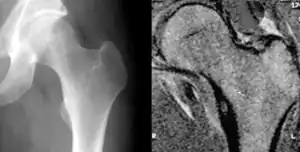

| Osteoid osteoma of the lesser trochanter: X-ray and MRI with marked sclerosis around the nidus | |